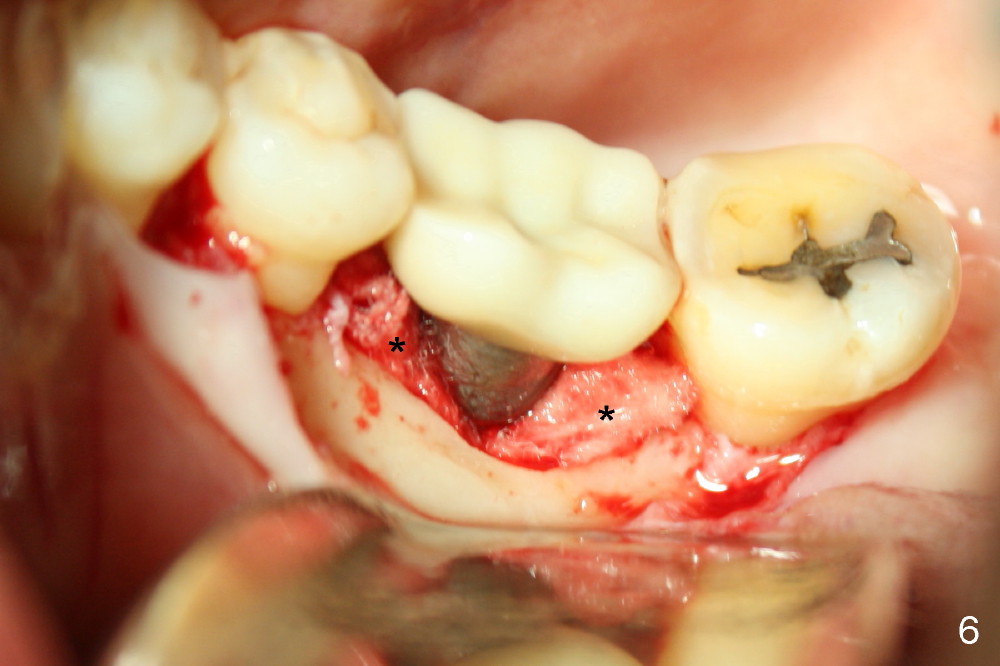

Upon flap reflection and granulation tissue curettage, the lingual threads are shown to be exposed with mesial bone resorption (Fig.5 <). The lingual defect is soaked with Clindamycin saturated gauzes (Fig.6 *), followed by copious irrigation, Emdogain application, bone graft and collagen dressing. The flap is sutured and covered by perio dressing.